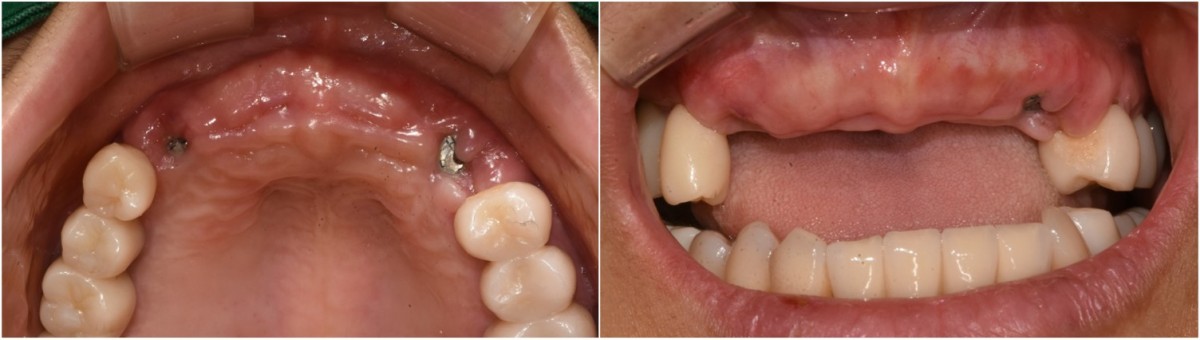

A 46-year-old female patient didn’t

have any systemic problems but a poor oral condition.

The patient is scheduled

for the implant and general prosthetic restoration in various parts. First of

all, the vertical stop is completed by several prostheses in the posterior

region, and the final stage of intraoral restoration is to proceed with an

anterior implant installation.